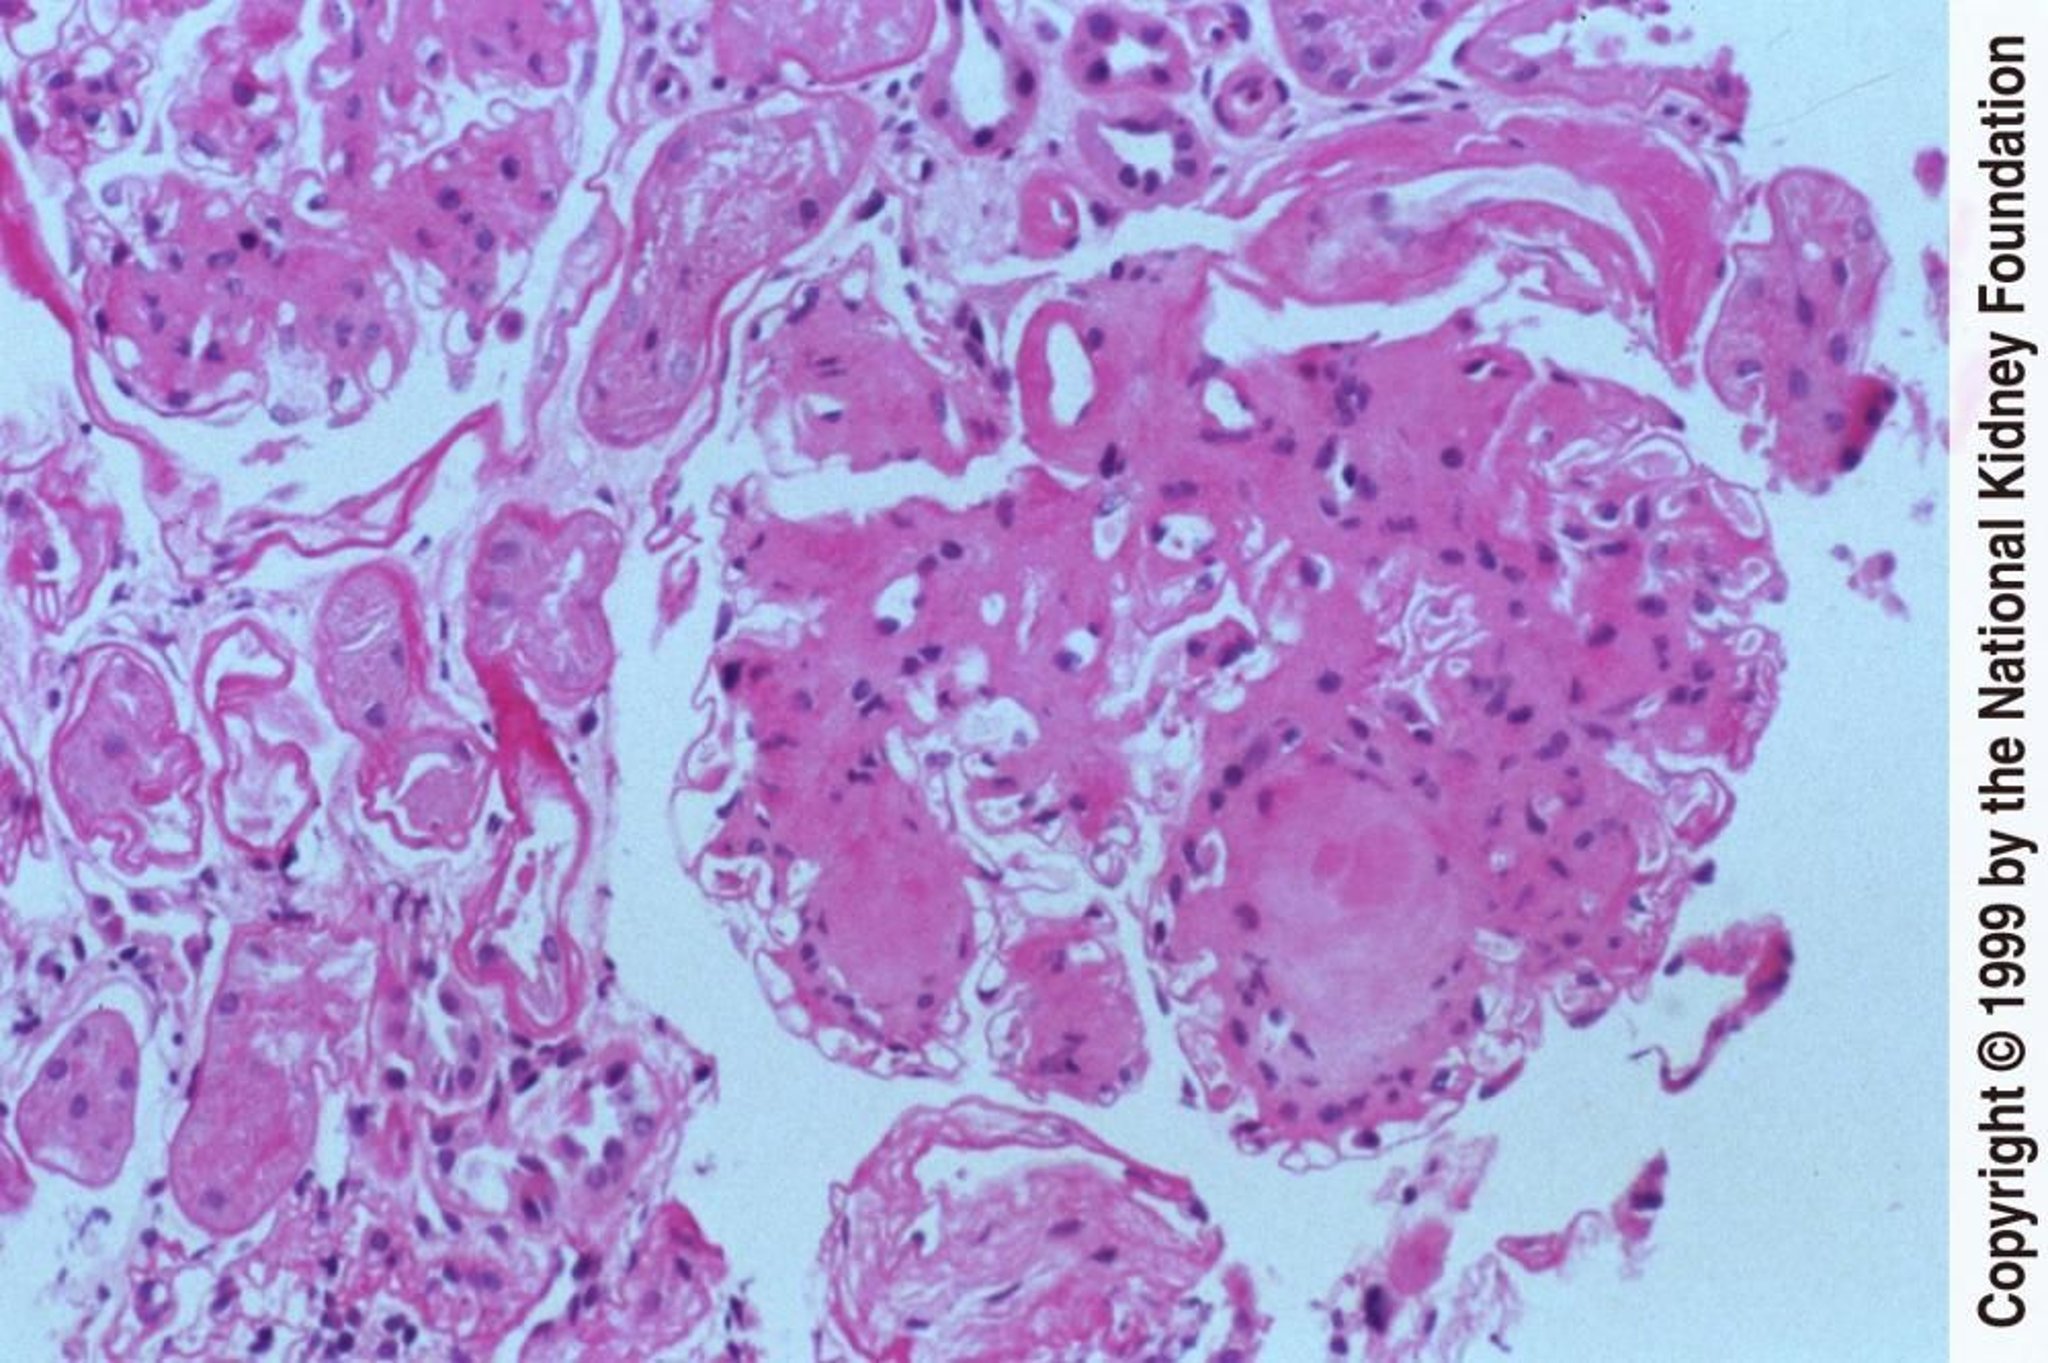

Nefropatia diabética (nódulos)

A formação de nódulos acelulares dentro da matriz mesangial é uma característica distintiva da nefropatia diabética (coloração com ácido periódico de Schiff, × 200).

Image provided by Agnes Fogo, MD, and the American Journal of Kidney Diseases' Atlas of Renal Pathology (see www.ajkd.org).